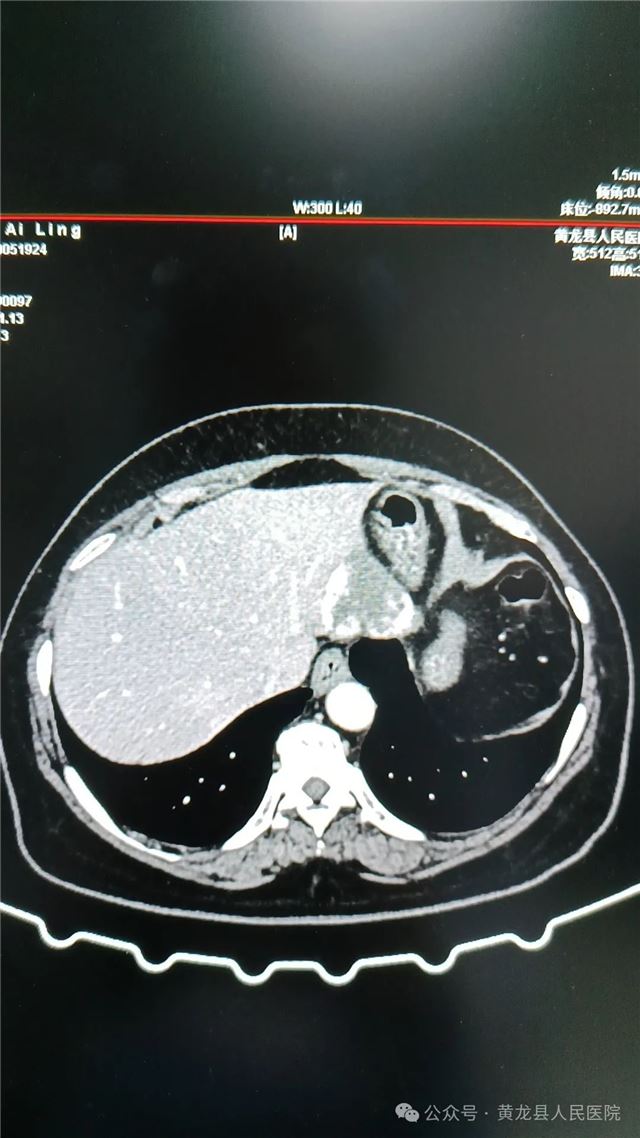

1,术前上腹部CT(平扫、增强)

患者女,58岁,在体检时发现肝占位性病变,经进一步检查后确诊“肝血管瘤”。